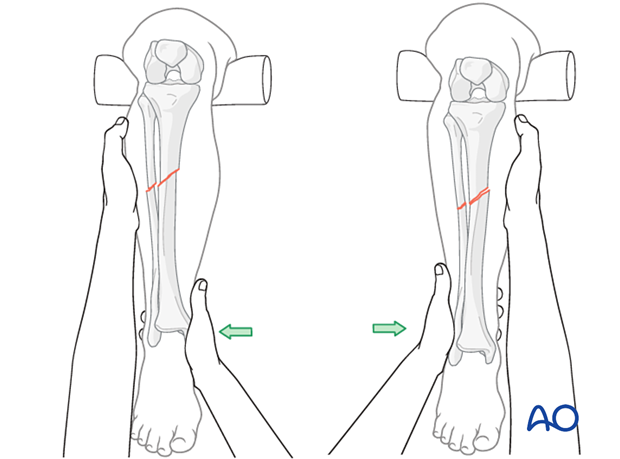

The illustration shows manual traction at the ankle to correct length.

This illustration shows correction of varus or valgus deformity.

This illustration shows correction of AP angulation.

Rotation is usually corrected by palpation of the tibial crest, or with the help of an imaginary alignment of the middle of the second toe, the center of the ankle, and the tibial tubercle.